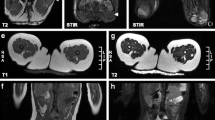

We found a significantly lower FA and higher MD (both p < 0.01) of the SLF in our cohort of classic infantile Pompe patients compared to the reference group (Fig. 1, Table 2), with a large effect size (Hedges G’. FA = 6.6, MD = − 11.5).

Anatomically, in contrast to the SLF, the PTR traverses through a relatively unaffected area as indexed by conventional MRI (T2-weighted, FLAIR). Group-level comparison of classic infantile patients and the reference group, showed a significantly lower FA and higher MD (p < 0.01), (Fig. 1, Table 2). However, the effect size (Hedges’ G) of these differences was smaller (FA 2.1, MD − 4.7) compared to the SLF.

We found a significant difference (p < 0.01) for all studied white matter tracts (Table 2, Fig. 1), with a lower FA and higher MD in patients compared to the reference population. Large-association tracts, such as the SLF, ILF and IFO, showed the largest differences in FA and MD between patients and controls, as reflected by Hedges G’ effect size. A smaller effect size was found for CST, as well as the thalamic radiations, such as the STR, PTR and ATR.

In patients without or with only mild T2 abnormalities (stage 0 or 1), FA values were within the reference range, while for patients with moderate or severe white matter abnormalities (stage 2 and 3), FA values were markedly lower. In general, patients with advanced white matter abnormalities (stage 3) on structural MRI, consistently showed the largest deviations in white matter microstructural metrics, compared to the reference sample (Fig. 2).

Tractography results of classic infantile patients and reference population. White matter tracts are sorted from left to right by effect size of FA. White matter tracts with a large effect size show larger differences between MRI stages. FA fractional anisotropy, MD medial diffusivity (*10−3mm2/s), SLF superior longitudinal fasciculus, ILF inferior longitudinal fasciculus, IFO inferior fronto-occipital fasciculus, CST cortico-spinal tract, PTR posterior thalamic radiation, ATR anterior thalamic radiation

Furthermore, in the white matter tracts with the largest deviations (i.e., largest Hedges G’ effect size) compared to the reference group (i.e., the SLF, ILF and IFO), the differences in FA or MD were larger between the MR stages, pointing at an ongoing process of further derailment from normal for the most severely affected tracts (Fig. 2). For example, for the SLF (FA reference range 0.33–0.46), median FA was 0.39 (range 0.39–0.40) for stage 1, 0.25 (range 0.22–0.29) for stage 2 and 0.19 (range 0.19–0.21) for stage 3, while for the PTR, the differences between the stages were less apparent (FA reference range 0.36–0.48), with a median FA of 0.42 (range 0.41–0.43) for stage 1, 0.39 (range 0.38–0.42) for stage 2 and 0.34 (range 0.33–0.35) for stage 3.